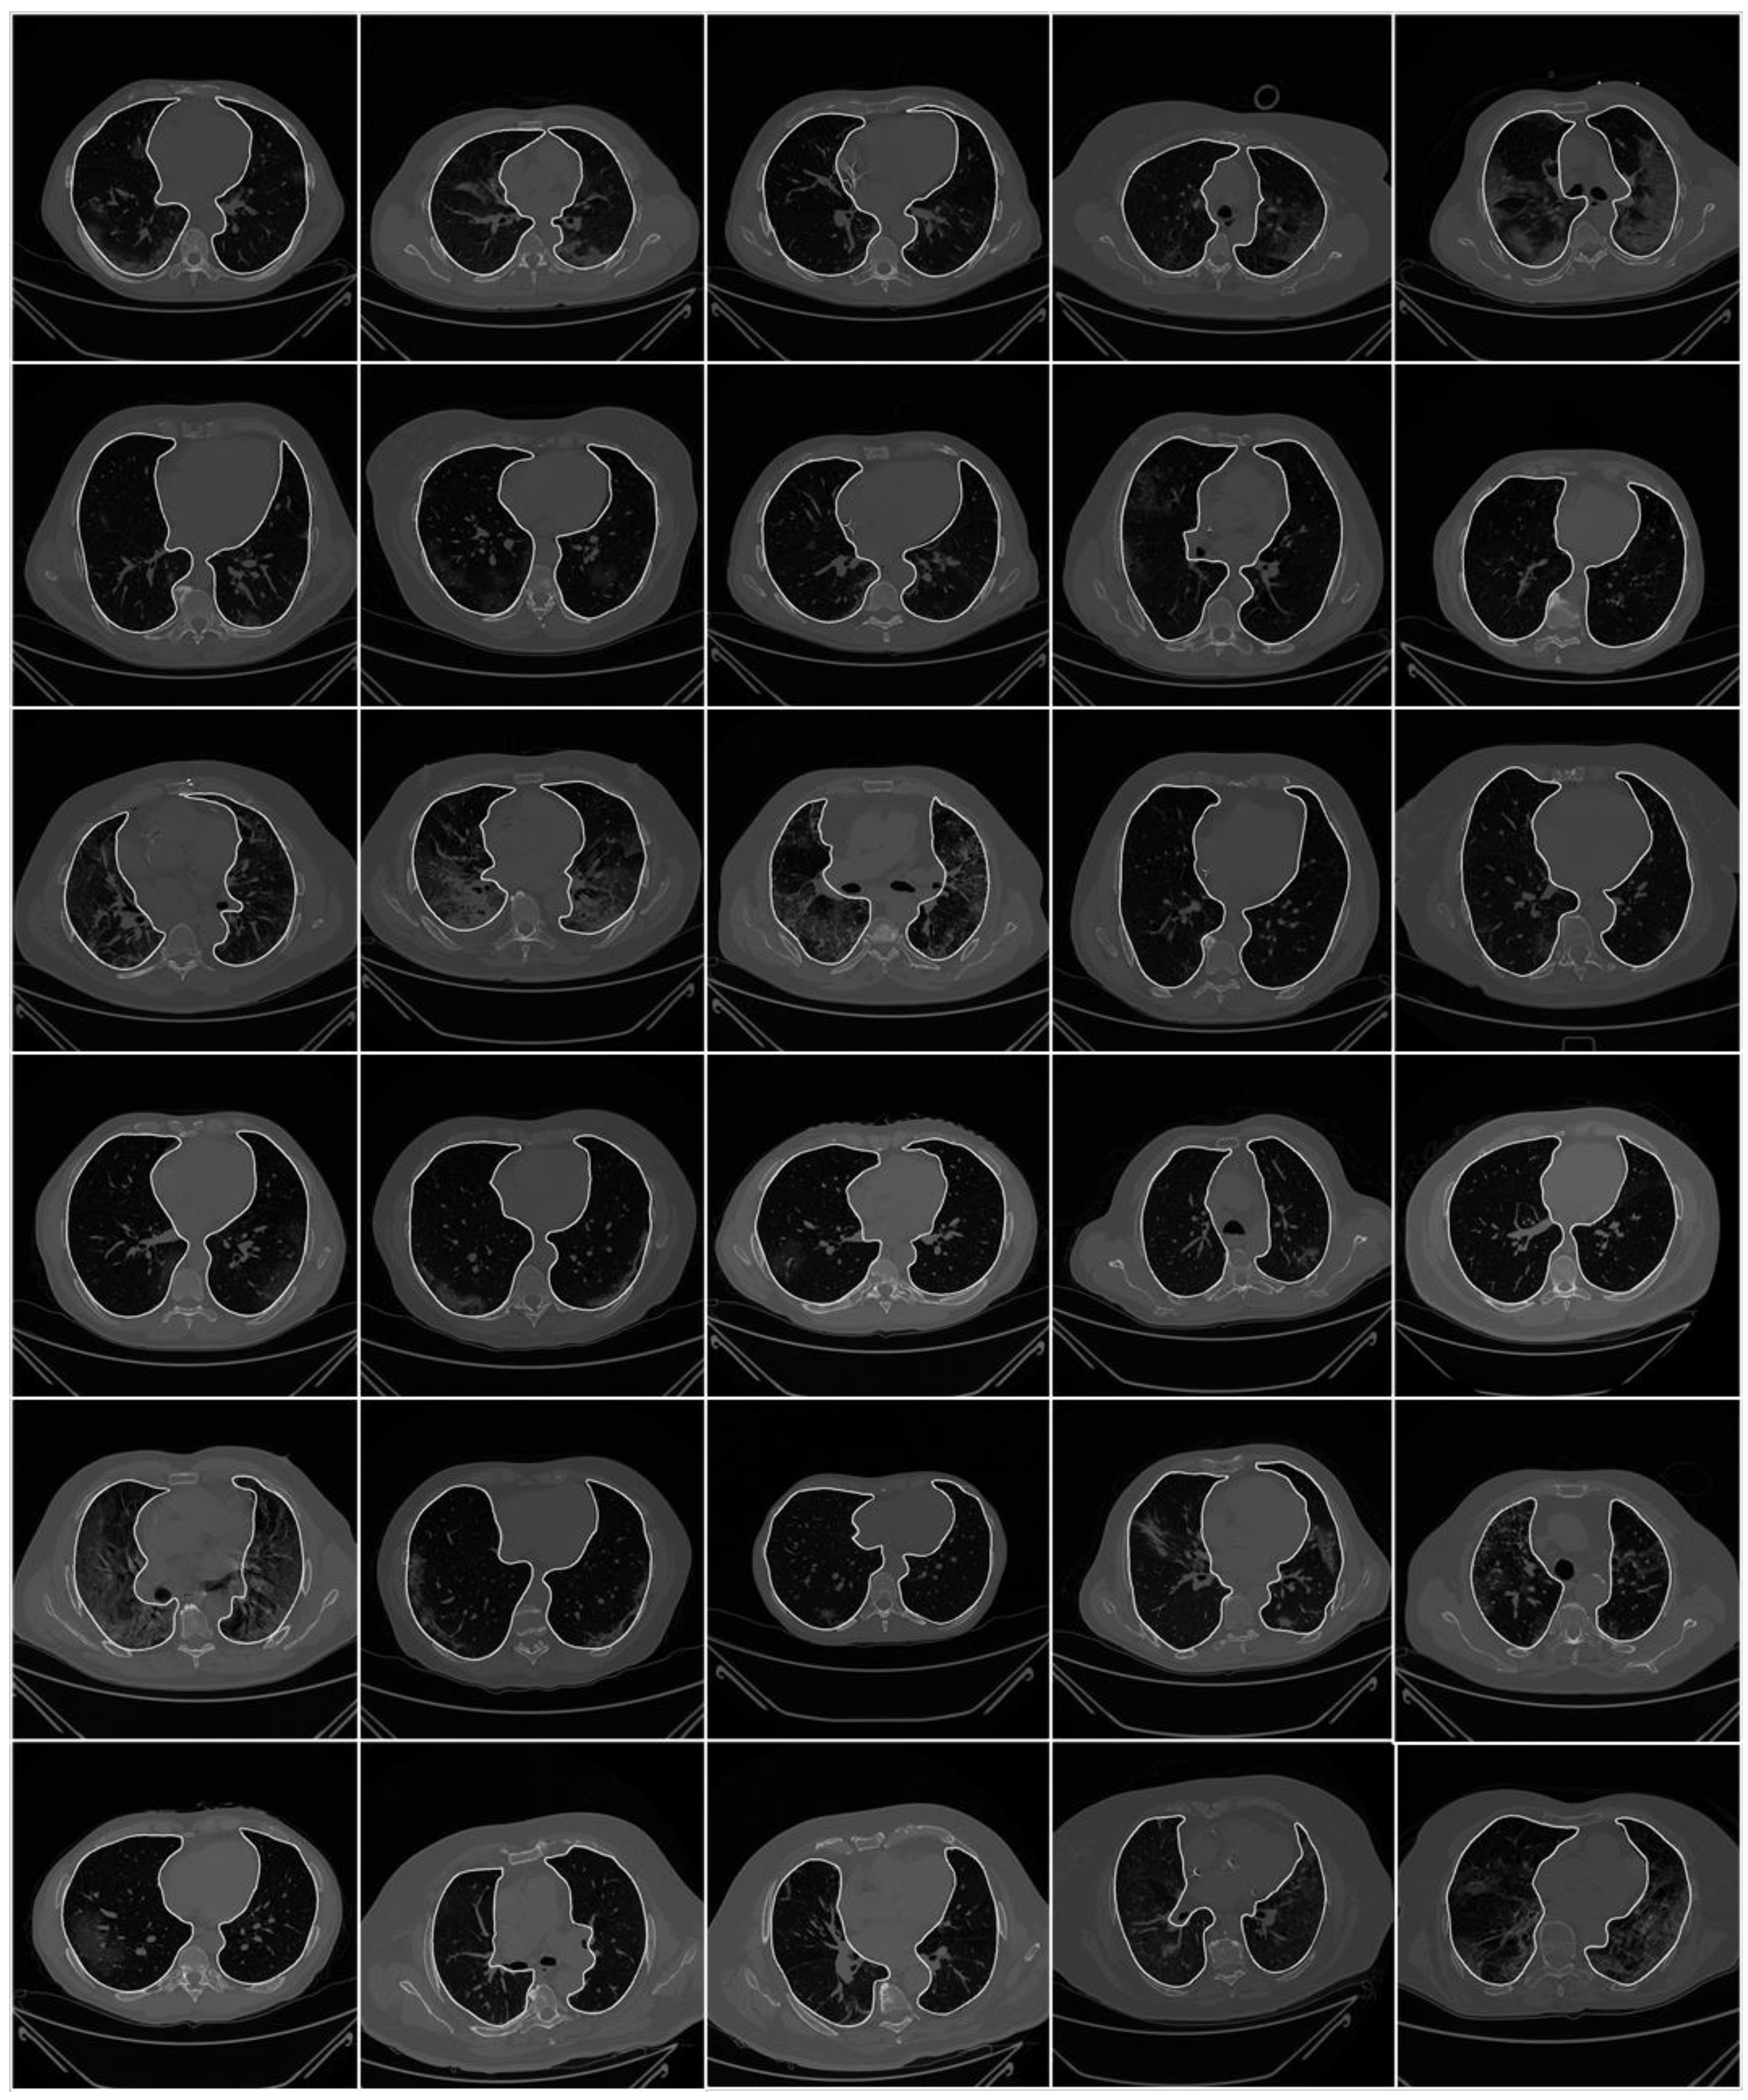

2.1. Patient Demographics, Image Acquisition, and Data Preparation

2.1.2. Image Acquisition

2.1.3. Data Preparation